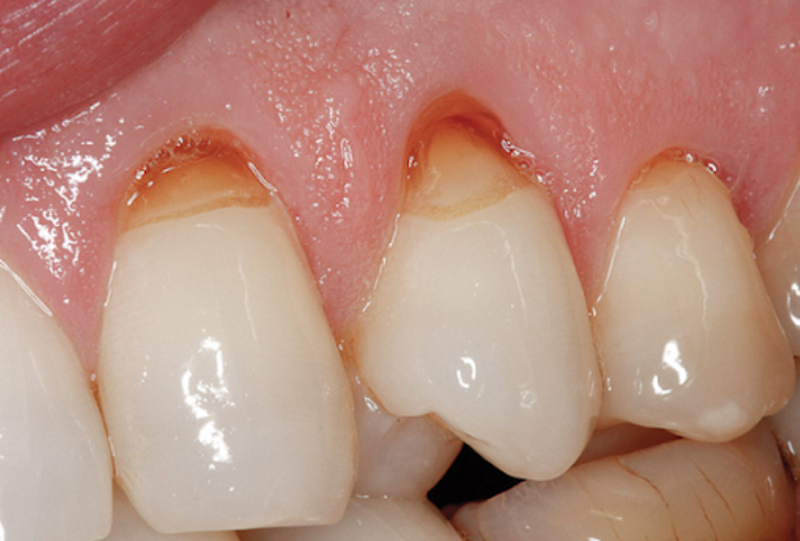

Mòn cổ chân răng là hiện tượng men răng ở vùng cổ chân răng bị mòn khuyết vào trong. Biểu hiện của tình trạng này là khi ăn uống hoặc hít không khí lạnh thì răng sẽ có cảm giác bị ê buốt. Đồng thời trên răng bị ăn mòn sẽ xuất hiện vết mòn hình chữ V.

Chân răng bị mòn là hiện tượng men răng ở vùng cổ chân răng bị mòn khuyết vào trongTheo các chuyên gia nha khoa thì bệnh chân răng bị mòn chủ yếu xảy ra bởi các nguyên nhân sau đây: